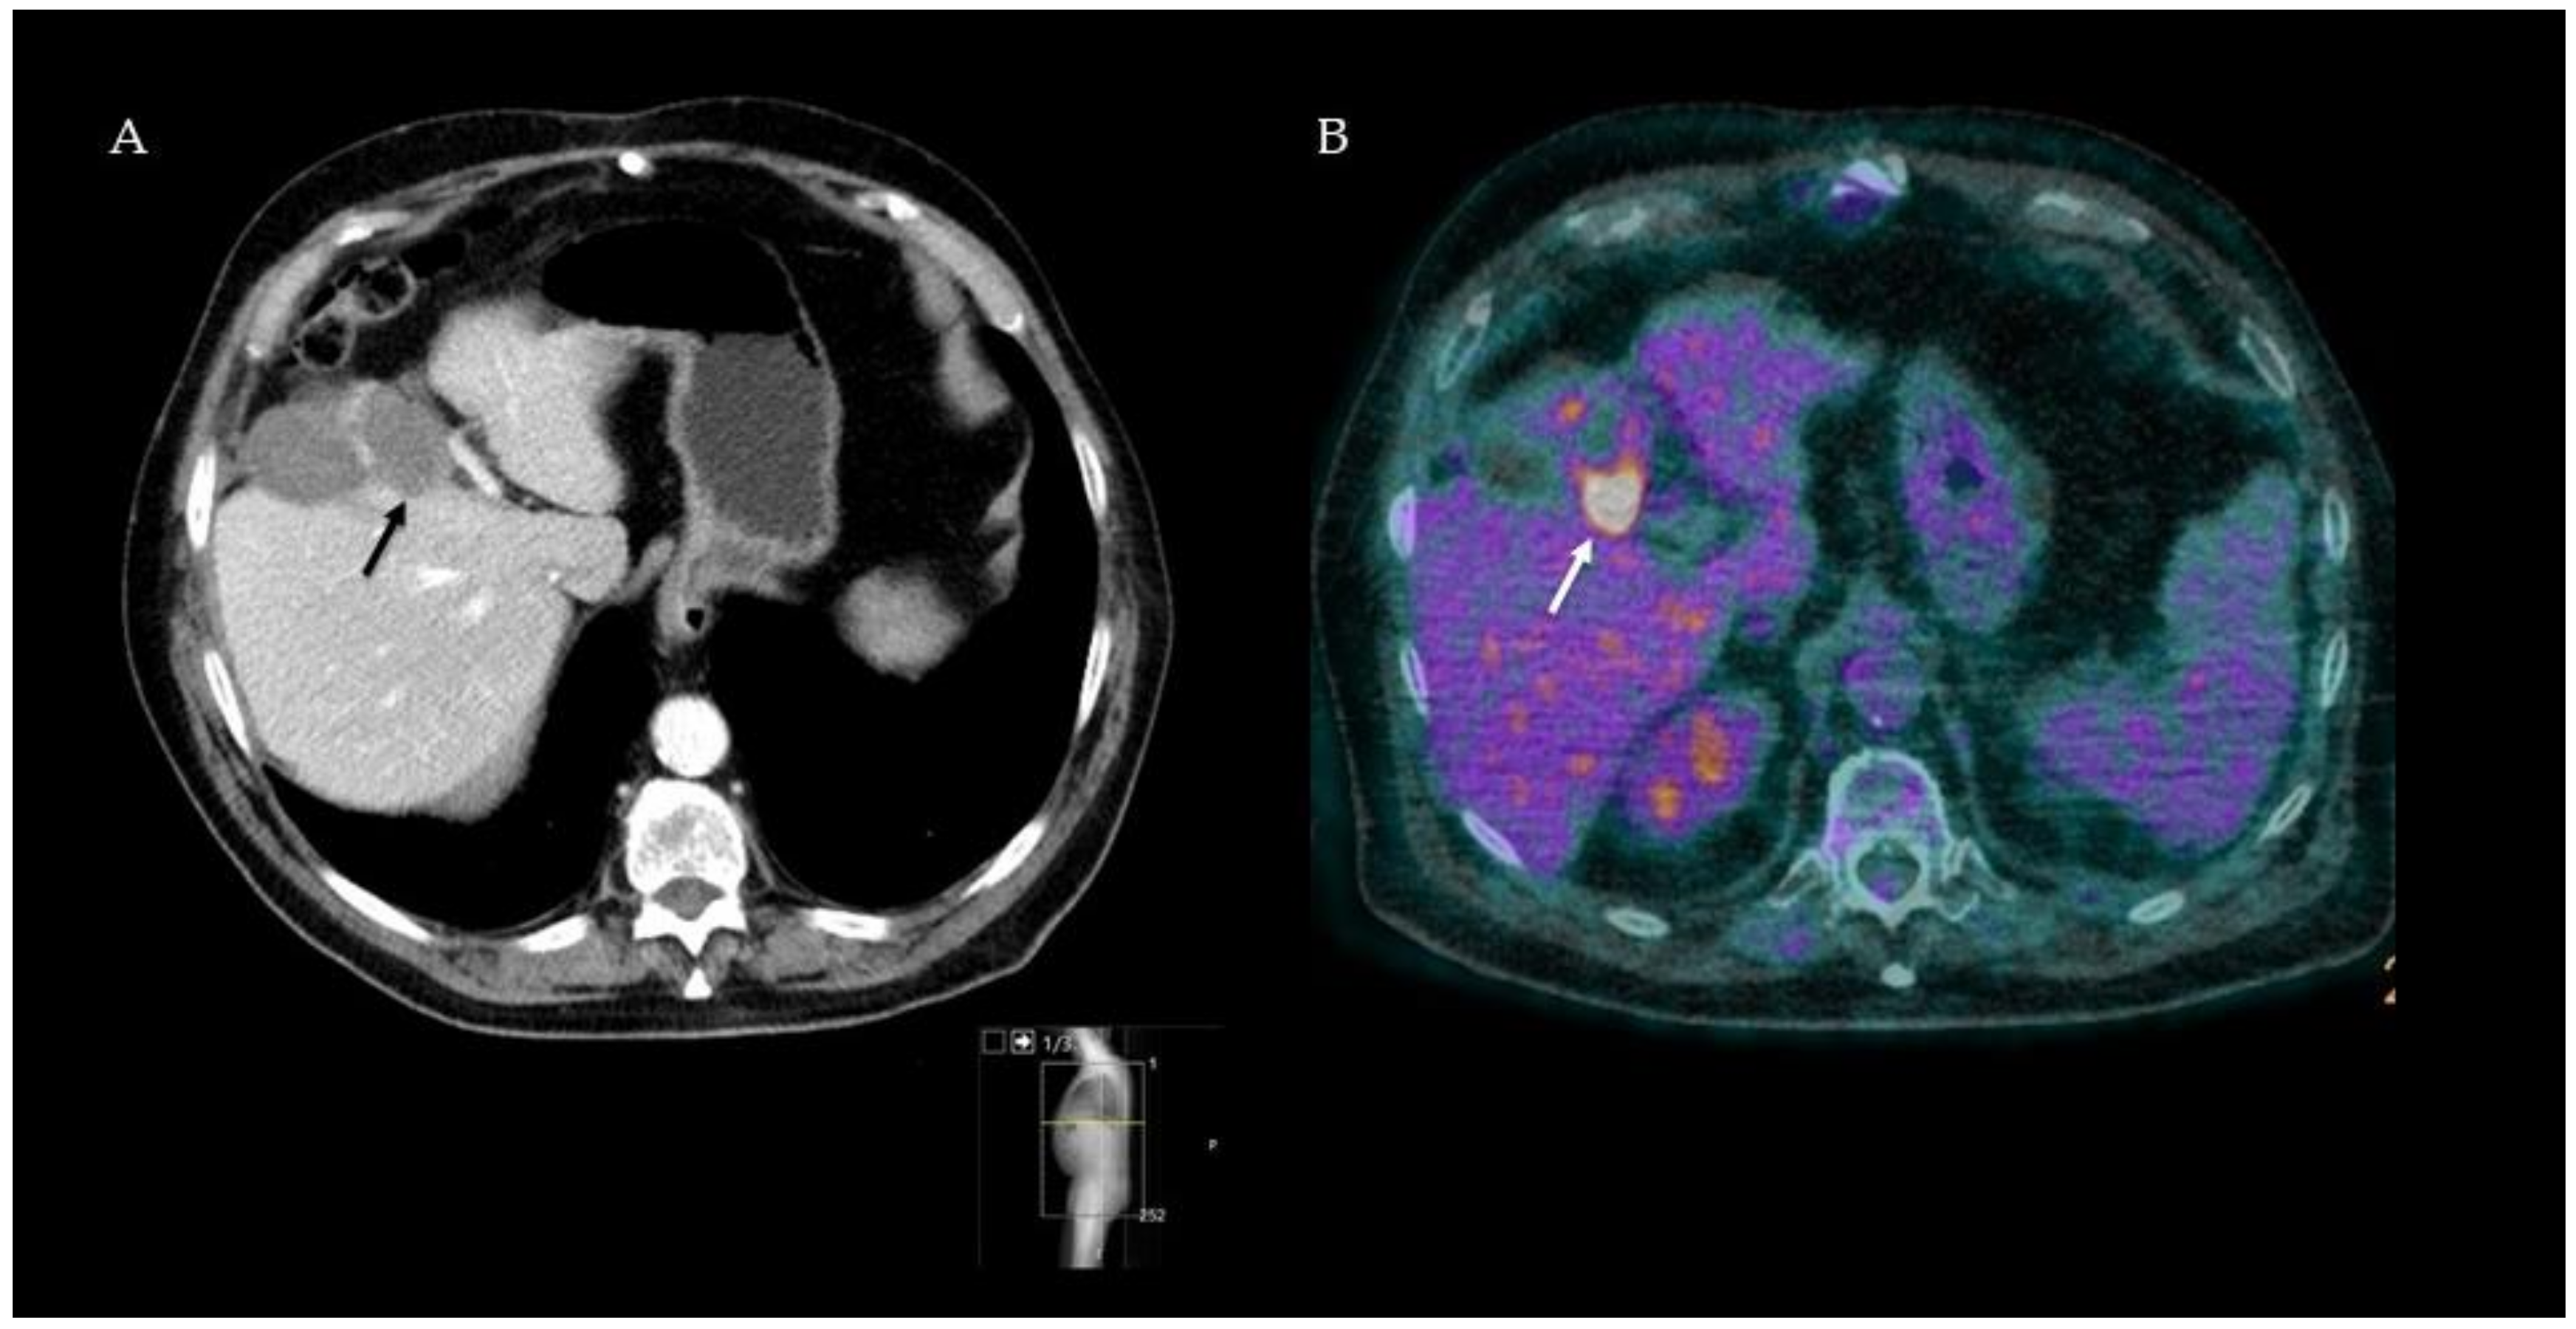

- Cornelis, F.; Sotirchos, V.; Violari, E.; Sofocleous, C.T.; Schoder, H.; Durack, J.C.; Siegelbaum, R.H.; Maybody, M.; Humm, J.; Solomon, S.B. 18F-FDG PET/CT Is an Immediate Imaging Biomarker of Treatment Success after Liver Metastasis Ablation. J. Nucl. Med. 2016, 57, 1052–1057. [Google Scholar] [CrossRef]

- Cornelis, F.H.; Petre, E.N.; Vakiani, E.; Klimstra, D.; Durack, J.C.; Gonen, M.; Osborne, J.; Solomon, S.B.; Sofocleous, C.T. Immediate Postablation 18F-FDG Injection and Corresponding SUV Are Surrogate Biomarkers of Local Tumor Progression After Thermal Ablation of Colorectal Carcinoma Liver Metastases. J. Nucl. Med. 2018, 59, 1360–1365. [Google Scholar] [CrossRef]